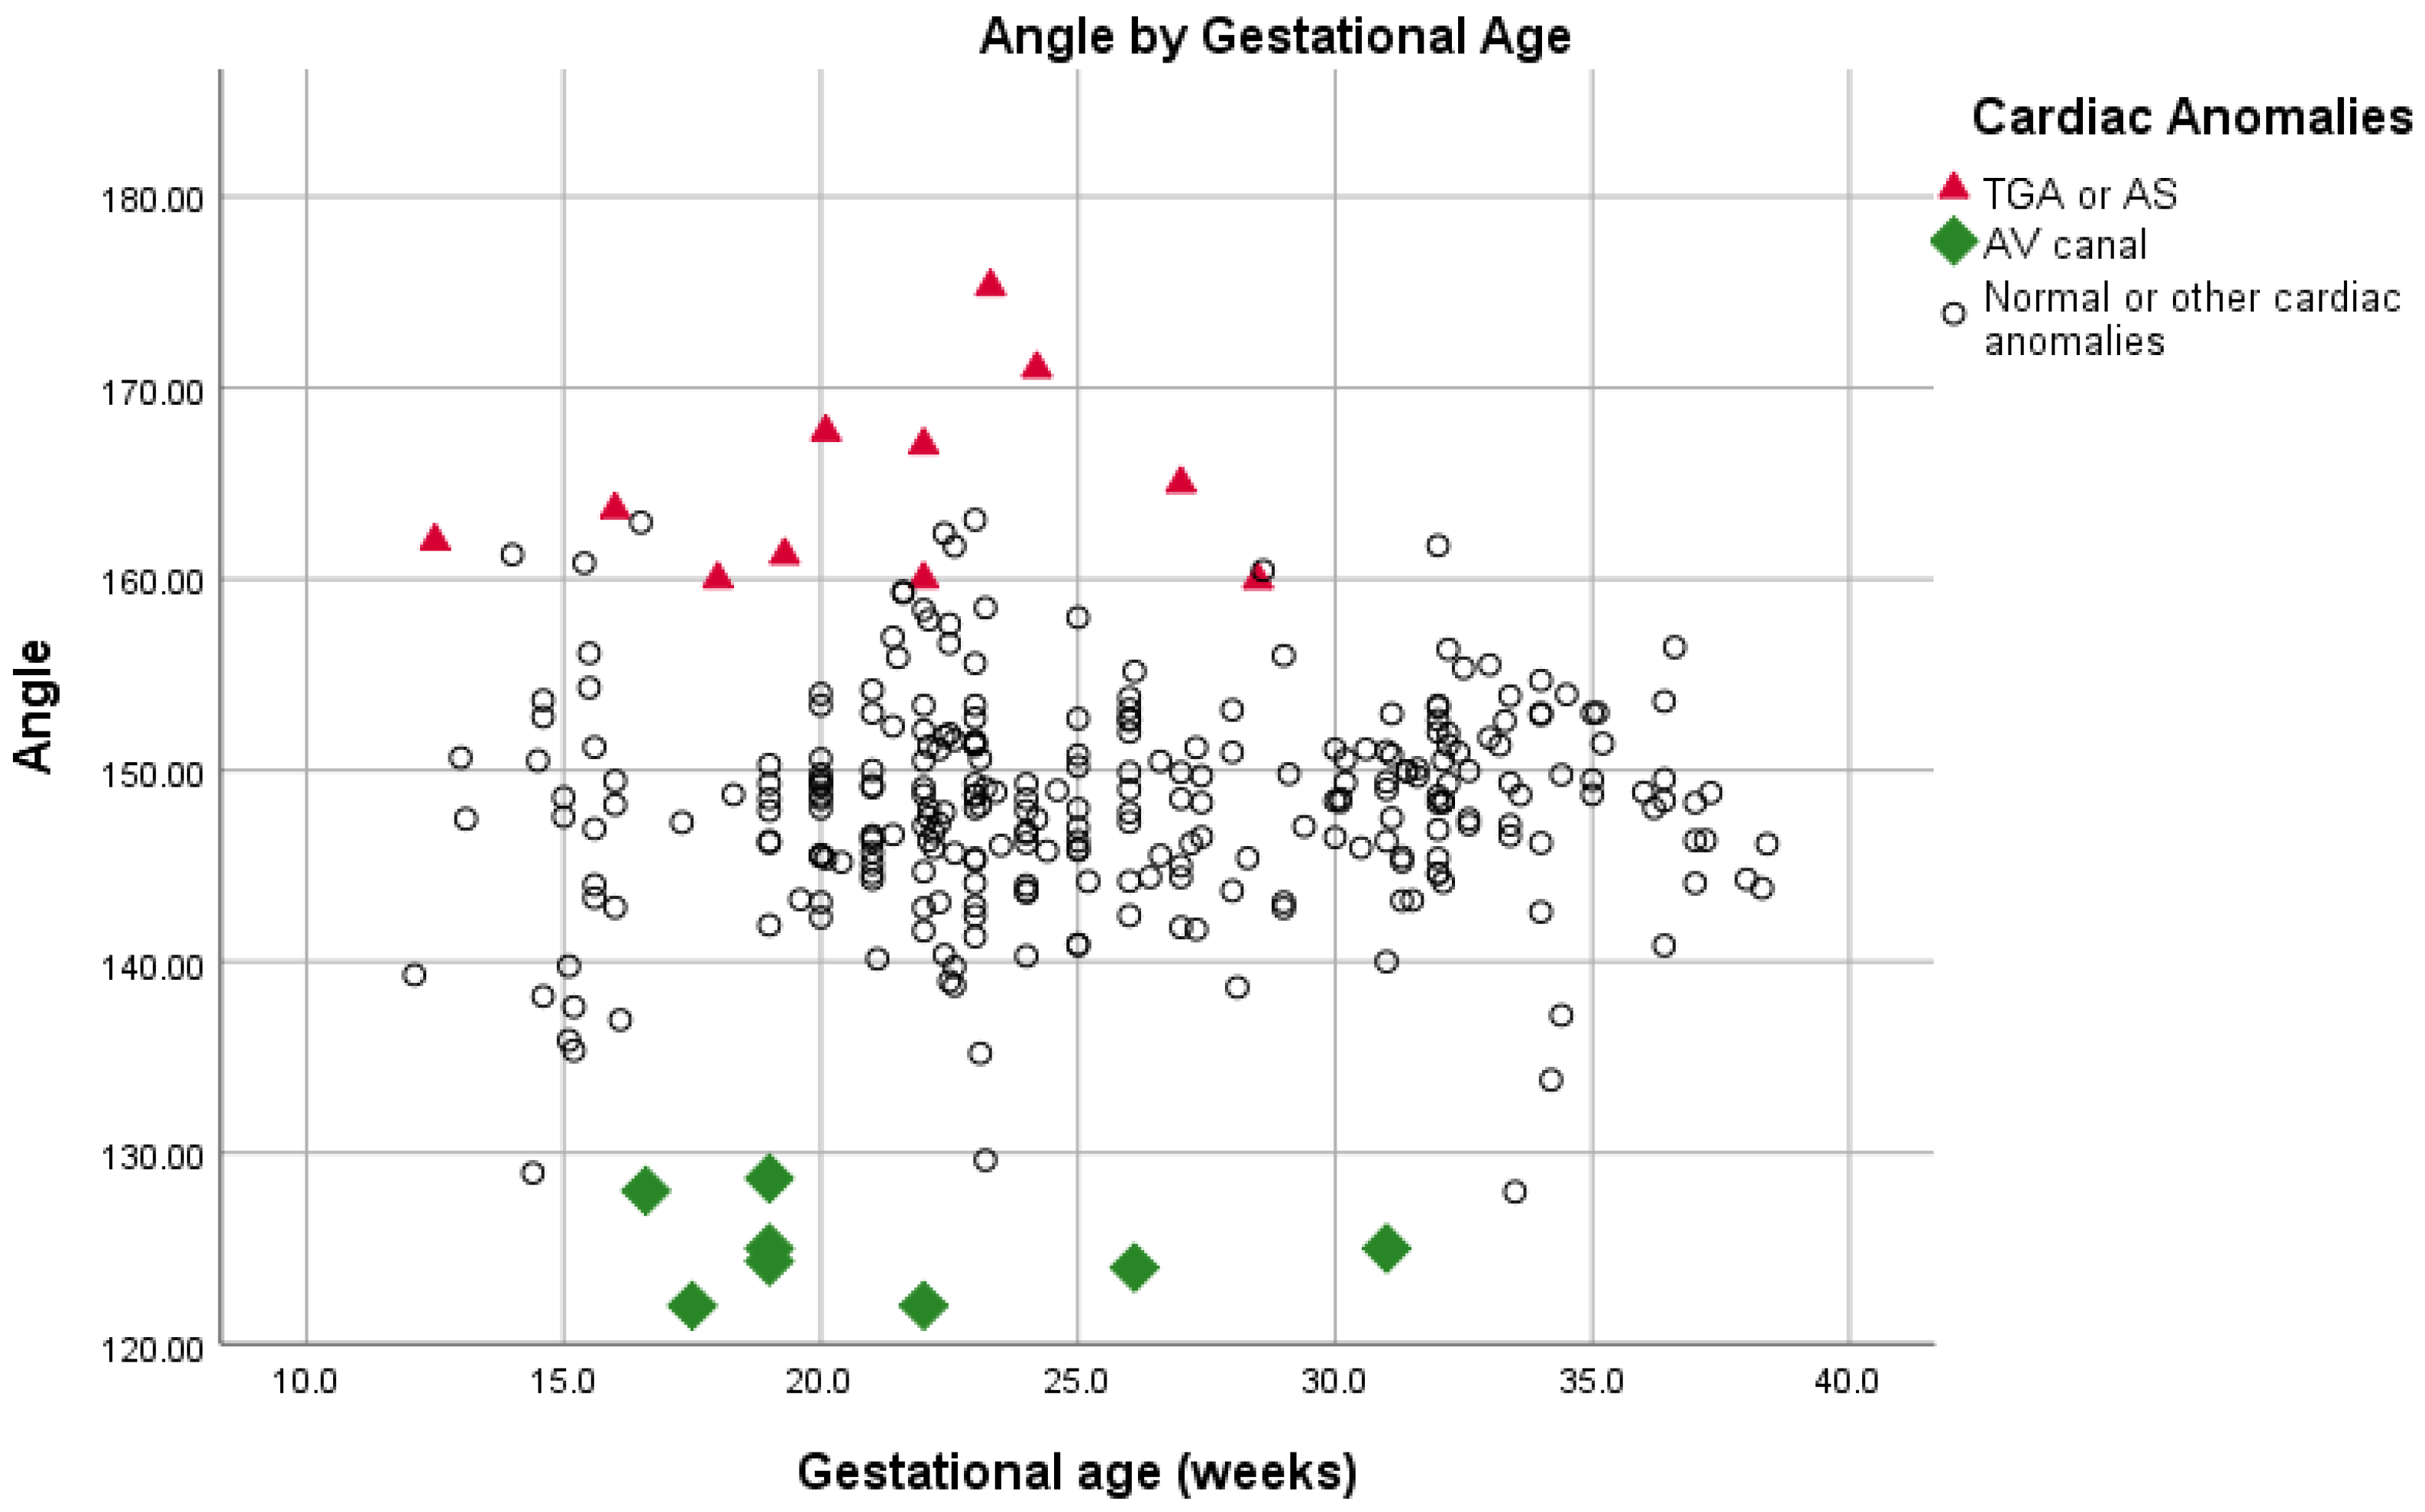

| Fetuses with Normal Hearts (n = 293) | AVC (n = 8) | p-Value | TGA/AS (n = 11) | p-Value | |

|---|---|---|---|---|---|

| Angle | 148.2 ± 5.4 (127–163) | 124.8 ± 2.4 (122–128.6) | <0.001 | 164.8 ± 5.0 (159.9–175.2) | <0.001 |